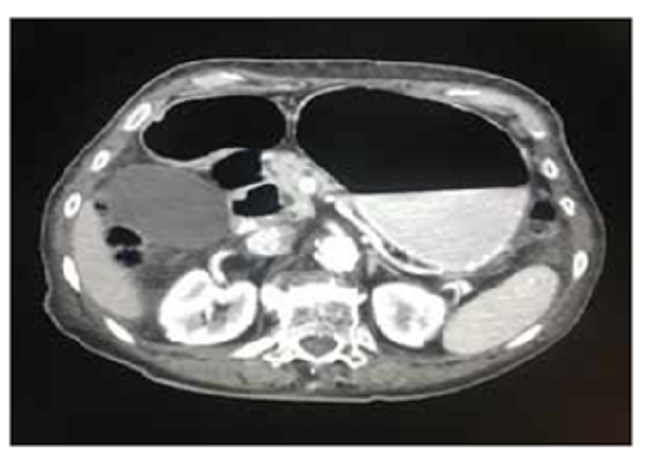

Por persistencia del cuadro clínico, se solicitó TC abdominal con contraste, en la que se apreció un íleo parcialmente obstructivo, hernia diafragmática derecha, dilatación esofágica indicativa de acalasia y derrame pleural y atelectasias en ambas bases pulmonares (figura 1 y 2.